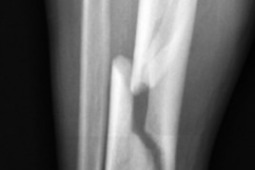

Mężczyźni częściej niż kobiety umierają po złamaniach będących wynikiem osteoporozy, wynika z badań przedstawionych na dorocznym spotkaniu American Academy of Orthopaedic Surgeons w dniach od 14 marca do 18 w San Diego.

Naukowcy przeanalizowali dane z ponad 1,6 miliona Amerykanów w wieku 65 lat i starszych, którzy mieli osteoporozę i doświadczyli złamań w latach 2005 i 2009. Spośród tych pacjentów, 87 procent stanowiły kobiety.

Śmiertelność w rok po złamaniu wynosiła 18,7 procent wśród mężczyzn i 13,9 procent wśród kobiet. Kobiety były pięć razy bardziej narażone na złamania początkowo niż mężczyźni, ale miał nieco mniejsze ryzyko kolejnych złamań w ciągu trzech lat od pierwszego złamania.

Wyniki te mogą być wykorzystywane do lepszego przygotowania pacjentów leczonych z powodu osteoporozy i doskonalenia narzędzi prognostycznych do monitorowania chorych.